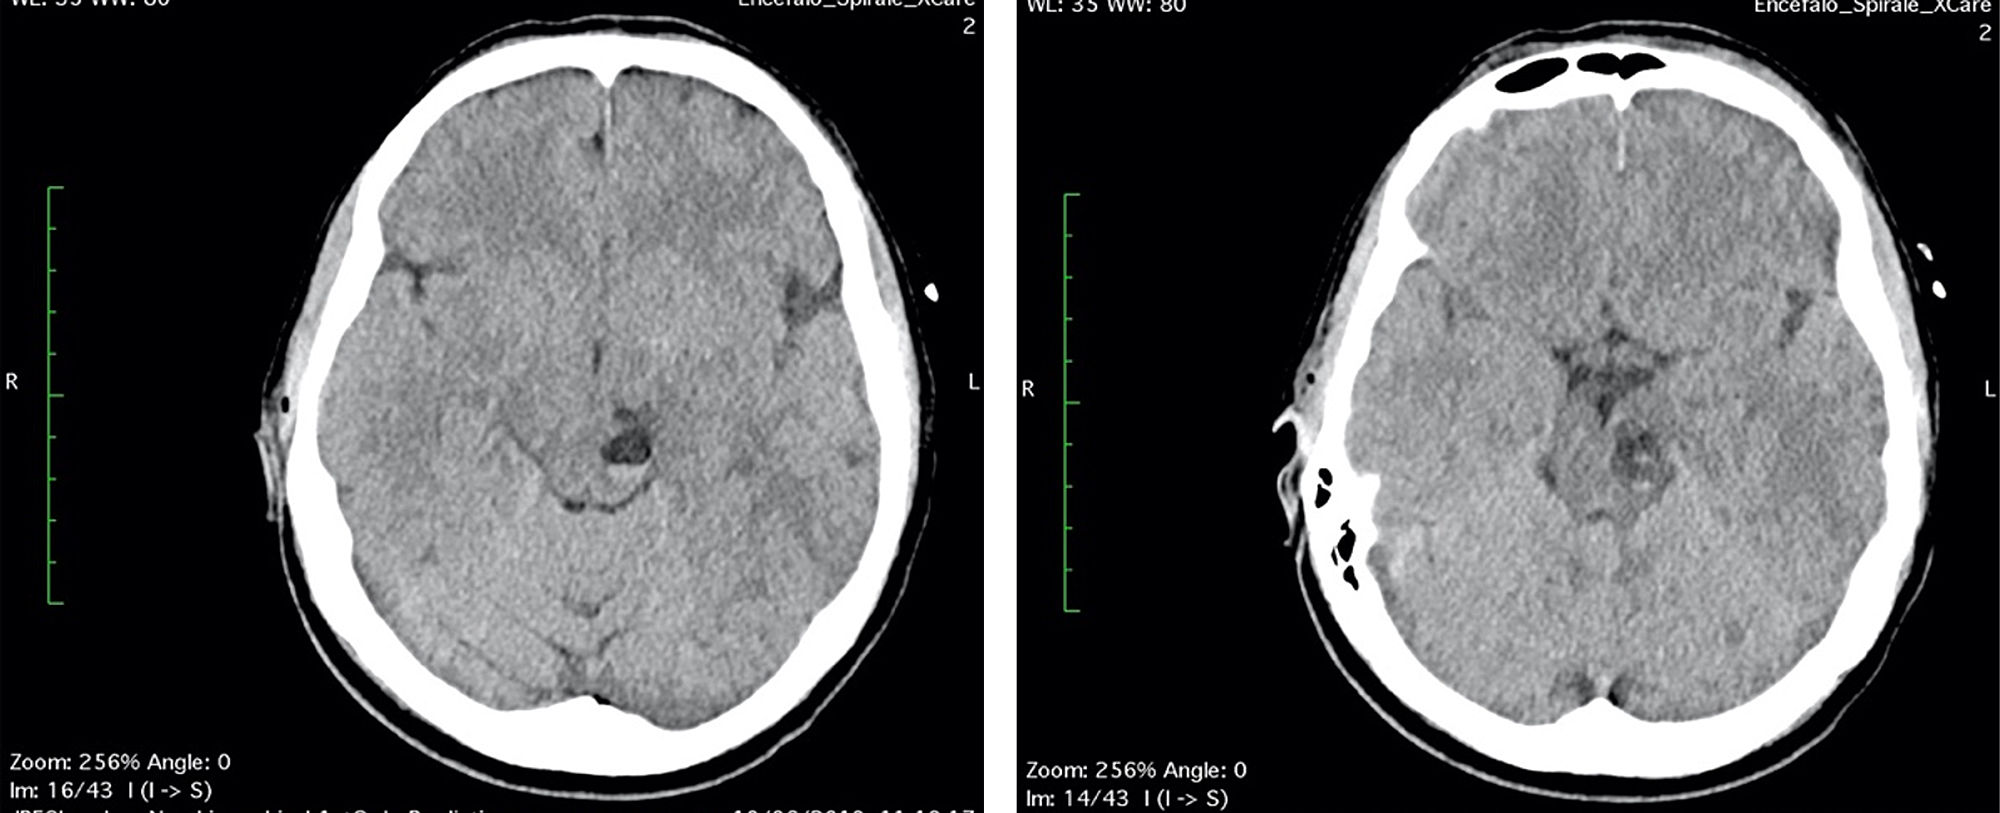

A 42-year-old woman, without previous disease, was admitted in the Emergency Room for a polytrauma during an accident car. Clinically she was conscious; she had a head trauma with hairy scalp; she complained headache and pain of the left foot; on the accident set, opiates were administered. Pressure of oxygen (PaO2) was 98%, cardiac frequency was 65 bpm, Glasgow Coma Scale was 15, and the neurological examination was negative. Laboratory tests revealed hemoglobin: 10.7 g/dL (normal range 12-16 g/dL), white blood cell: 11.71 x 109/L (normal range 4-10 x 109/L), coagulation tests in normal range, and normal platelet count. A total body CT was performed; it demonstrated, beyond the hairy scalp with large soft tissue loss in frontoparietal zone, a multiloculated cyst in the left midbrain, with eccentric hyper-density, hematic-like (Figure 1). An X-ray of the left foot showed a fracture of the first toe. In absence of neurological deficit, the patient immediately underwent surgery for the reconstruction of the scalp.

The first day after surgery, the patient was transfunded for hemoglobin 6.8 g/dL (normal range 12-16 g/dL), referring to scalp surgery. She complained headache, vertigo, nausea and diplopia, reflecting an involvement of the brainstem and the oculomotor nerves. A second CT and brain MRI with IV contrast were performed: CT scan showed a fluid-fluid level, with enlargement of left cerebral peduncle and a slight mass effect (Figure 2). MRI scan confirmed the same findings of fluid-fluid level, with enlargement of left cerebral peduncle and a slight mass effect; no contrast enhancement was observed: these findings were referred to enlargement of VRSs with post-traumatic bleeding. Neither SAH nor intracerebral hematomas were revealed (Figure 3). No neurosurgery was indicated but only clinical and imaging follow up.